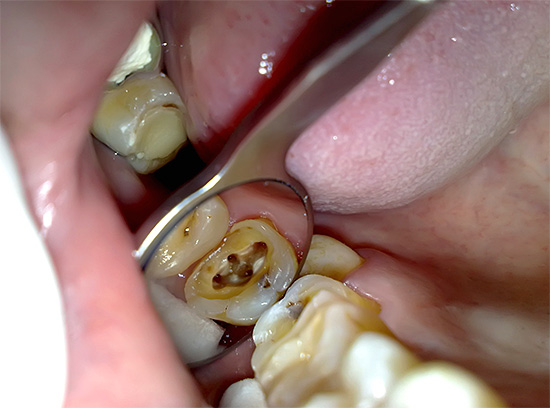

Nella fotografia sotto, i canali radicolari sono chiaramente visibili: ognuno di essi deve essere accuratamente pulito dai resti della polpa, altrimenti l'infezione conservata in essi può portare a gravi conseguenze in futuro: